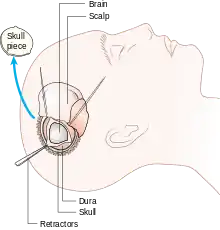

A craniotomy is a surgical operation in which a bone flap is temporarily removed from the skull to access the brain. Craniotomies are often critical operations, performed on patients who are suffering from brain lesions, such as tumors, blood clots, removal of foreign bodies such as bullets, or traumatic brain injury (TBI), and can also allow doctors to surgically implant devices, such as deep brain stimulators for the treatment of Parkinson's disease, epilepsy, and cerebellar tremor. The procedure is also used in epilepsy surgery to remove the parts of the brain that are causing epilepsy.

Human craniotomy is usually performed under general anesthesia but can be also done with the patient awake using a local anaesthetic; the procedure, typically, does not involve significant discomfort for the patient. In general, a craniotomy will be preceded by an MRI scan which provides an image of the brain that the surgeon uses to plan the precise location for bone removal and the appropriate angle of access to the relevant brain areas. The amount of skull that needs to be removed depends on the type of surgery being performed. The bone flap is mostly removed with the help of a cranial drill and a craniotome, then replaced using titanium plates and screws or another form of fixation (wire, suture, etc.) after completion of the surgical procedure. In the event the host bone does not accept its replacement, an artificial piece of skull, often made of PEEK, is substituted. (The PEEK appliance is routinely modeled by a CNC machine capable of accepting a high resolution MRI computer file in order to provide a very close fit, in an effort to minimize fitment issues, and therefore minimizing the duration of the cranial surgery.)